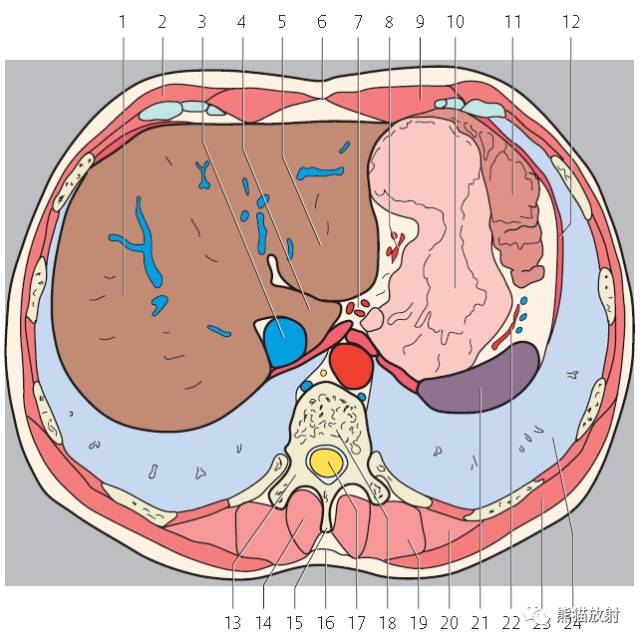

第一层

左上图中的阿拉伯数字提示“肝段”

1、肝右叶;2、腹外斜肌;3、下腔静脉;4、肝尾状叶;5、肝左叶;6、腹白线;7、腹腔干;8、胃左动脉;9、腹直肌;10、胃;11、结肠左曲;12、膈肌;13、椎弓;14、棘肌;15;棘突;16、胸腰筋膜;17、椎管和脊髓;18、胸椎;19、最长肌;20、髂肋肌(胸段);21、脾脏;22、胃后动脉;23、背阔肌;24、左肺;25、肋膈隐窝;26、右膈下隐窝;27、肝裸区;28、肋间淋巴结;29、贲门;30、膈上淋巴结;31、后纵隔;32、心切迹;33、膈下淋巴结;34、左侧结肠旁沟。